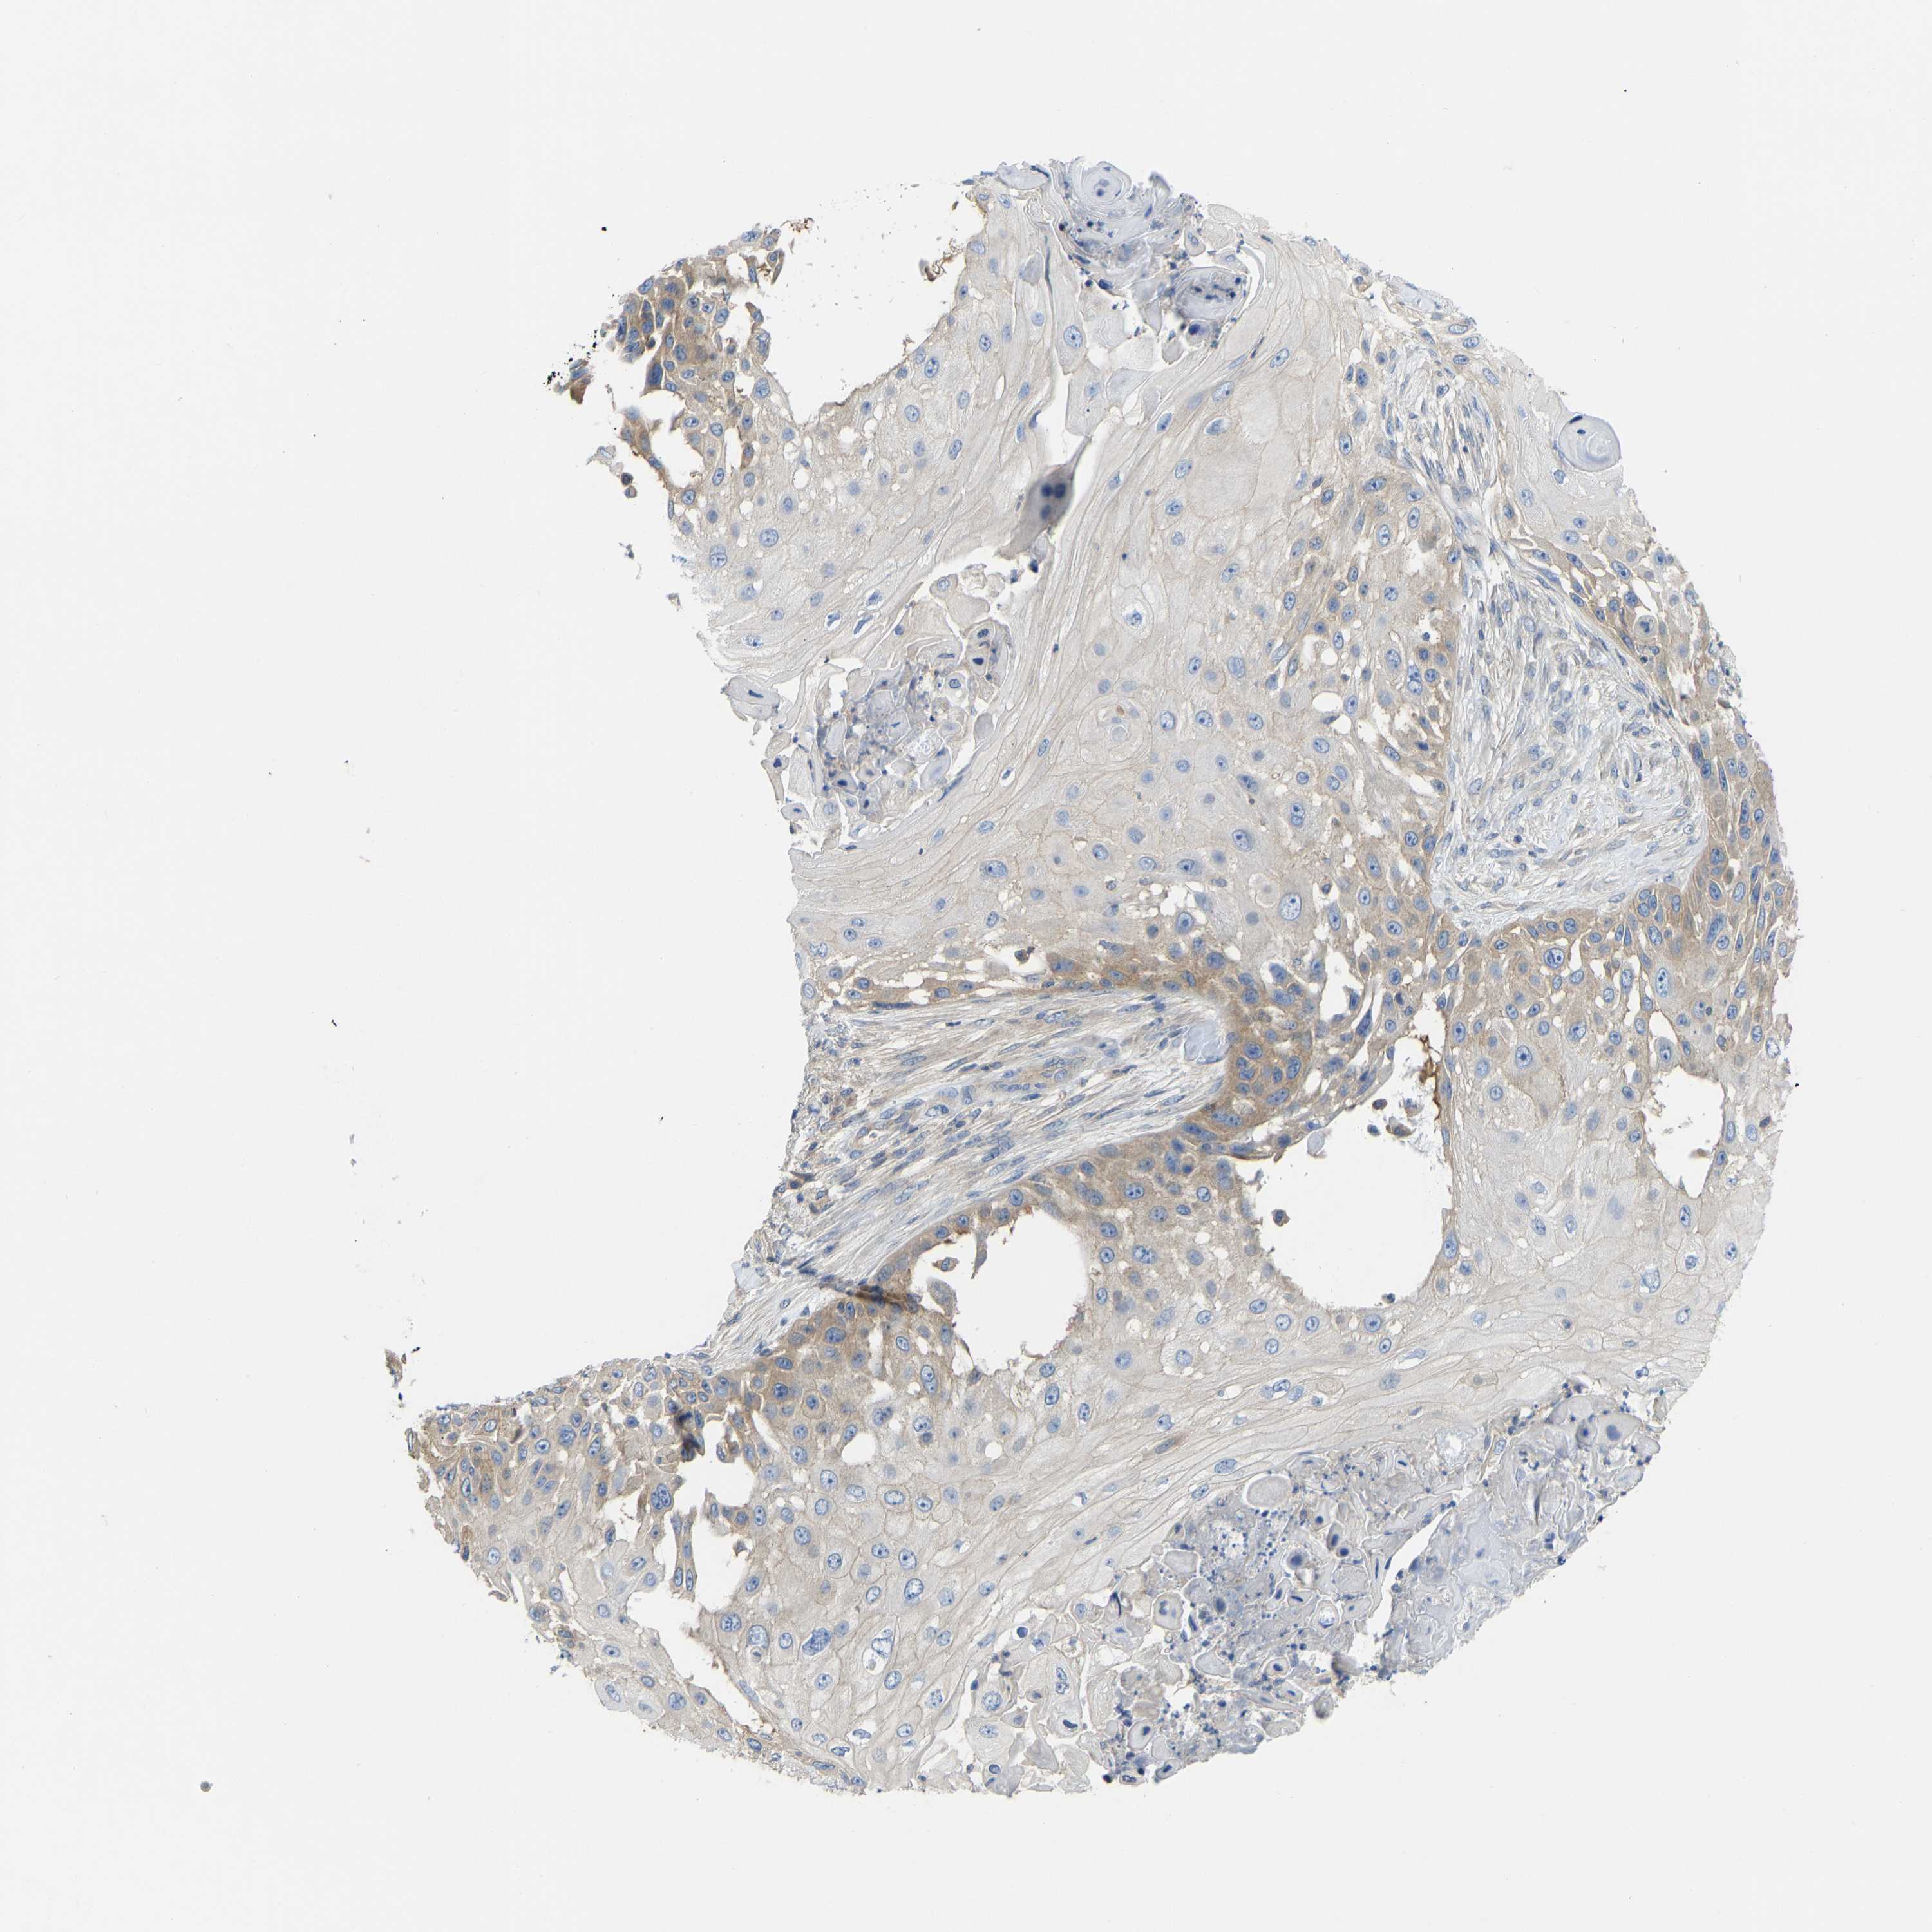

SKIN CANCER - Protein expressioni

A mouse-over function shows sample information and annotation data. Click on an image to view it in a full screen mode. Samples can be filtered based on level of antibody staining by selecting one or several of the following categories: high, medium, low and not detected. The assay and annotation is described here.

Antibody stainingi

Antibody staining in the annotated cell types in the current human tissue is reported as not detected, low, medium, or high, based on conventional immunohistochemistry profiling in selected tissues. This score is based on the combination of the staining intensity and fraction of stained cells.

Each image is clickable and will lead to virtual microscopy that enables deeper exploration of all samples and also displays staining intensity scores, fraction scores and subcellular localization as well as patient and tissue information for each sample.

Antibody CAB018581

Squamous cell carcinoma, NOS